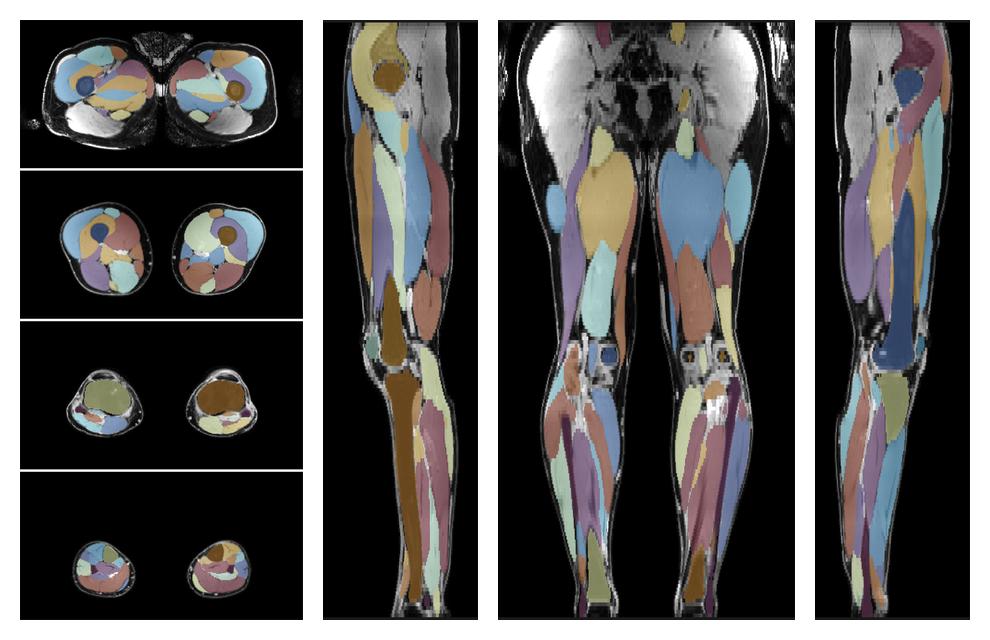

• Automated muscle and bone segmentation.

Overlay of automated muscle segmentation labels on dixon water image.